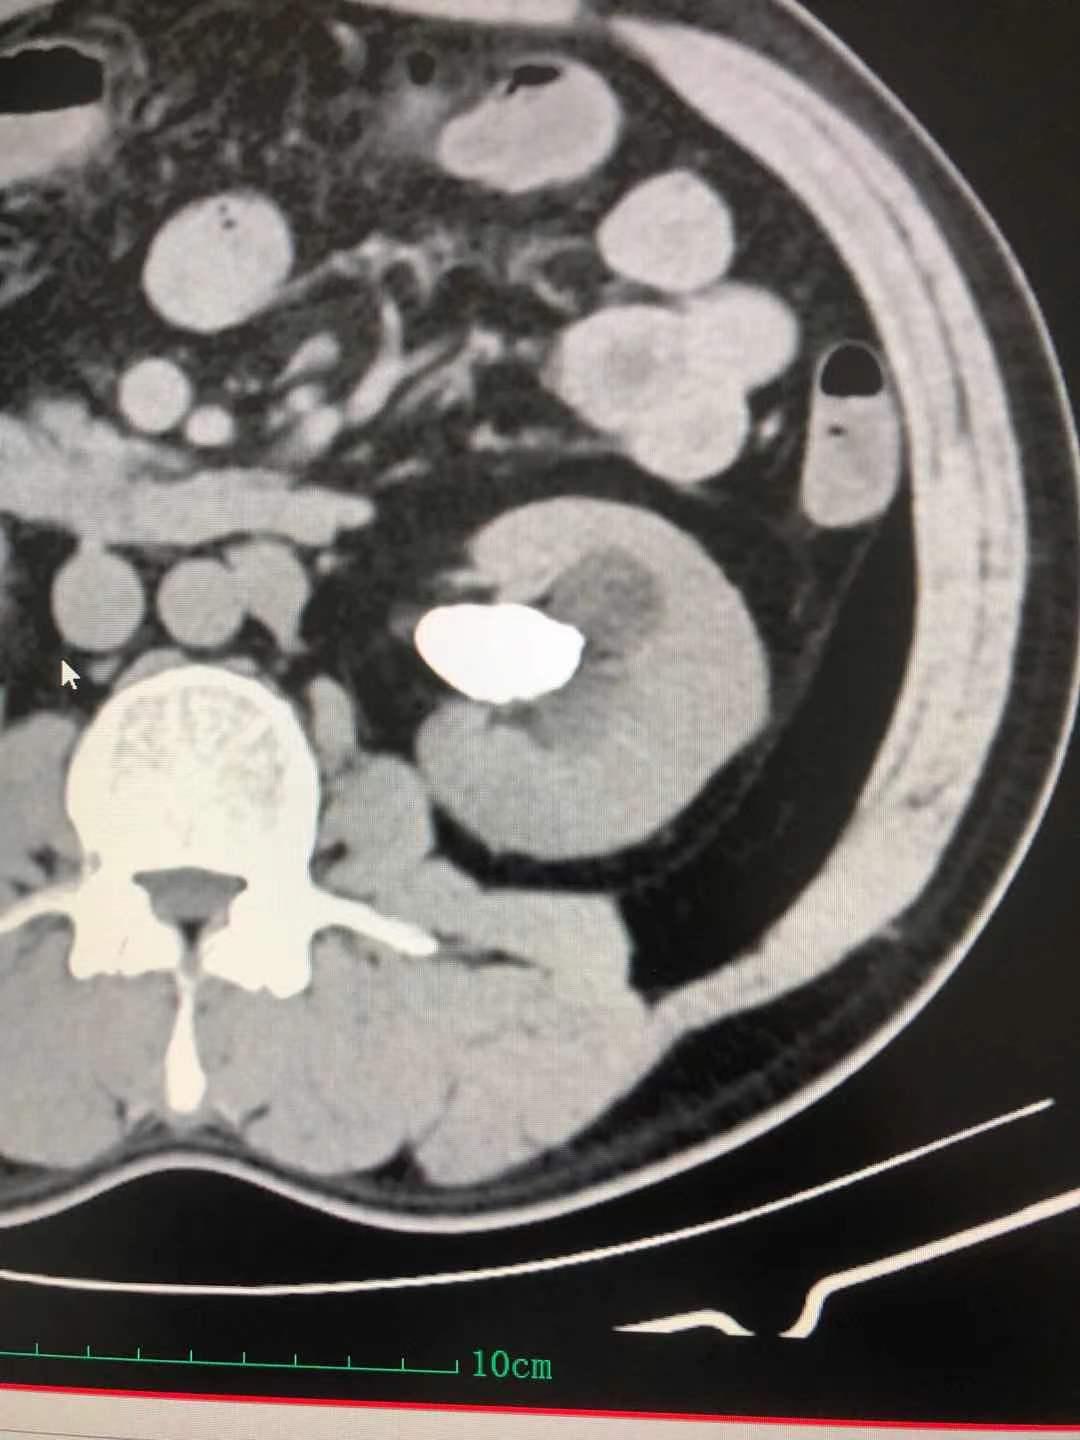

患者,男,40岁,以“间断性左侧腰腹部酸疼不适1月半”,入住我院泌尿外科。患者1月半前无明显诱因,出现左侧腰腹部间断性轻度酸疼不适,无恶心反胃,无寒战、发热,无咳嗽、咳痰,无尿频、尿急、尿痛,无肉眼血尿,3天前在利辛县某医院查腹部CT显示:左肾多发结石伴肾积水,最大结石约31mmX18mm,其就诊医生告诉患者其结石较大,需到省级以上医院就诊。患者经多方打听到我院可以治疗较大肾结石,遂来我院就诊。门诊医师以“左肾结石”收住入院。

入院后泌尿外科张国田主任仔细阅读患者泌尿系CT,诊断患者为左肾铸形结石合并肾盏结石,经过科室讨论,决定行“经皮肾镜左肾结石碎石取石术”。

积极术前准备,由手术室配合在全麻下行“经皮肾镜左肾结石碎石取石术”,手术历时约一个小时完成,不仅击碎并取净了肾盂内的铸形结石,连肾盏内的结石也一并击碎取出,术后患者恢复良好,于1周后出院,为表示感谢,特地送来一面锦旗。